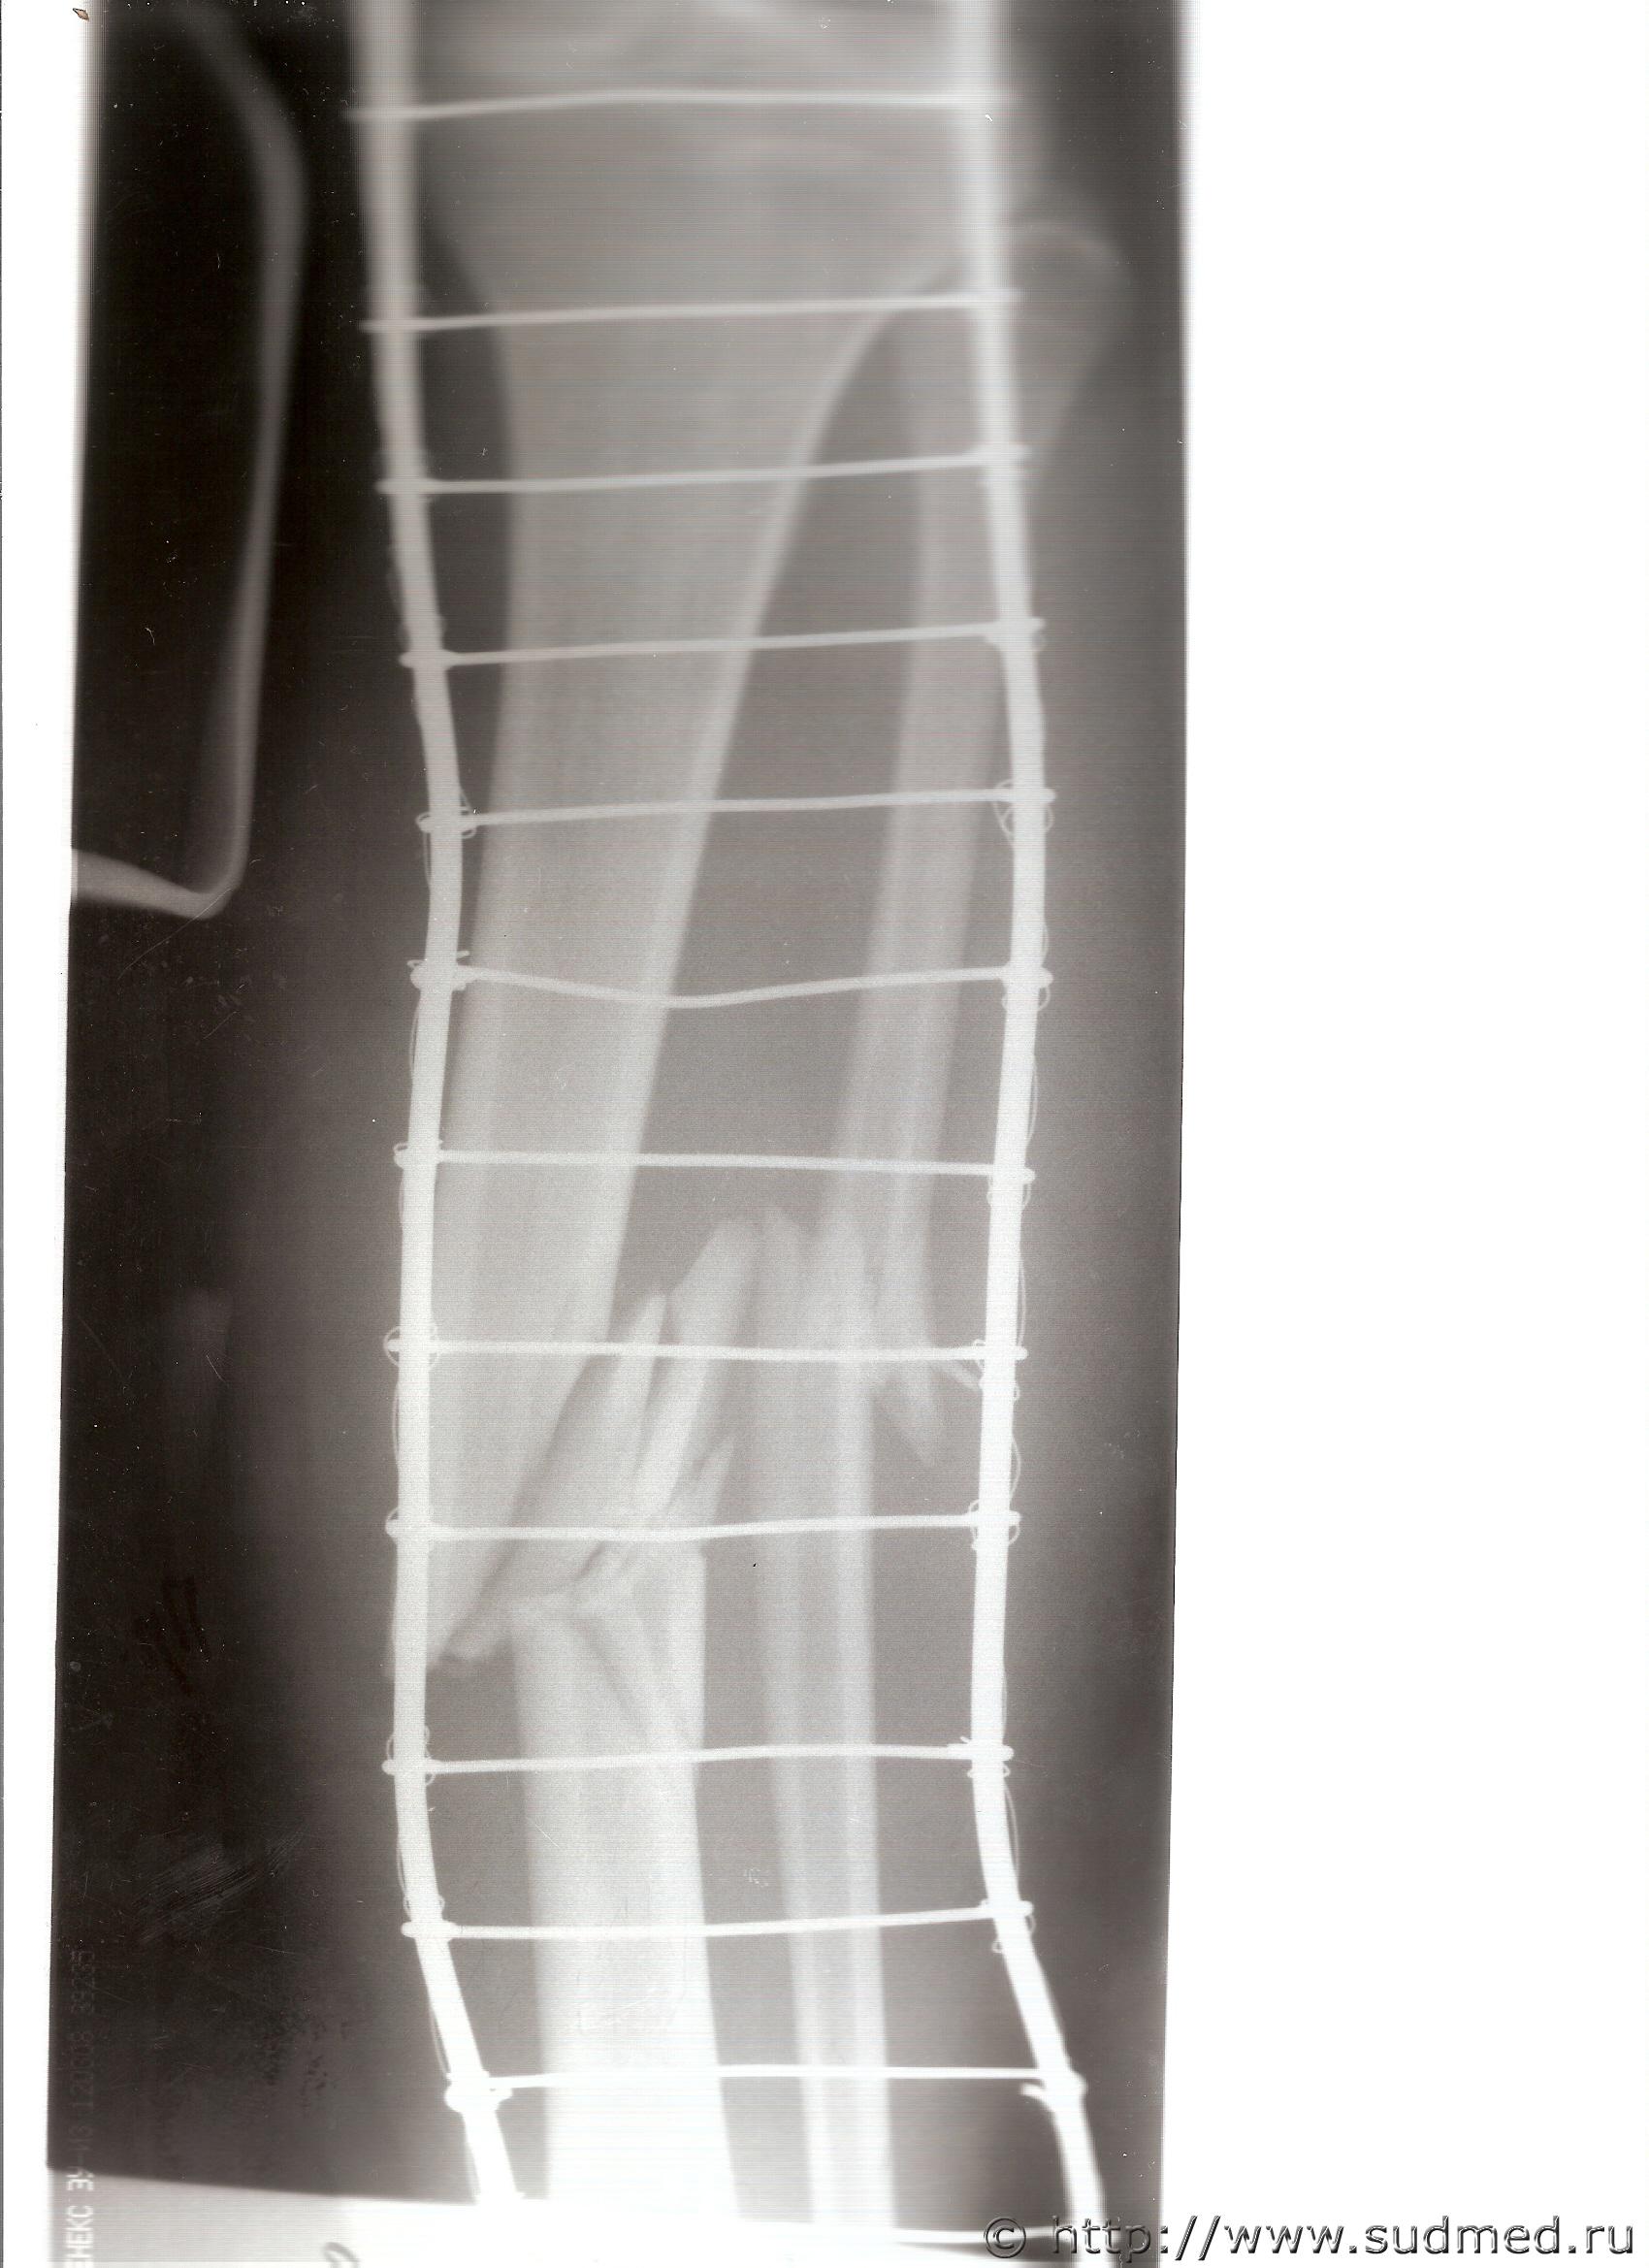

Хочу показать вам рентген, на ваш взгляд, здесь возможна средняя тяжесть?

Цитата(natasha30 @ 4.07.2011 - 17:35)

ТЯЖКИЙ вред. Без вариантов.

100% - тяжкий вред.